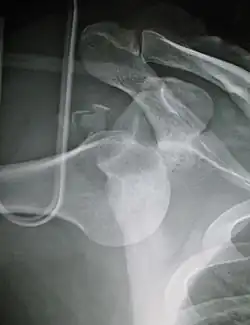

Anterior dislocation of the left shoulder.